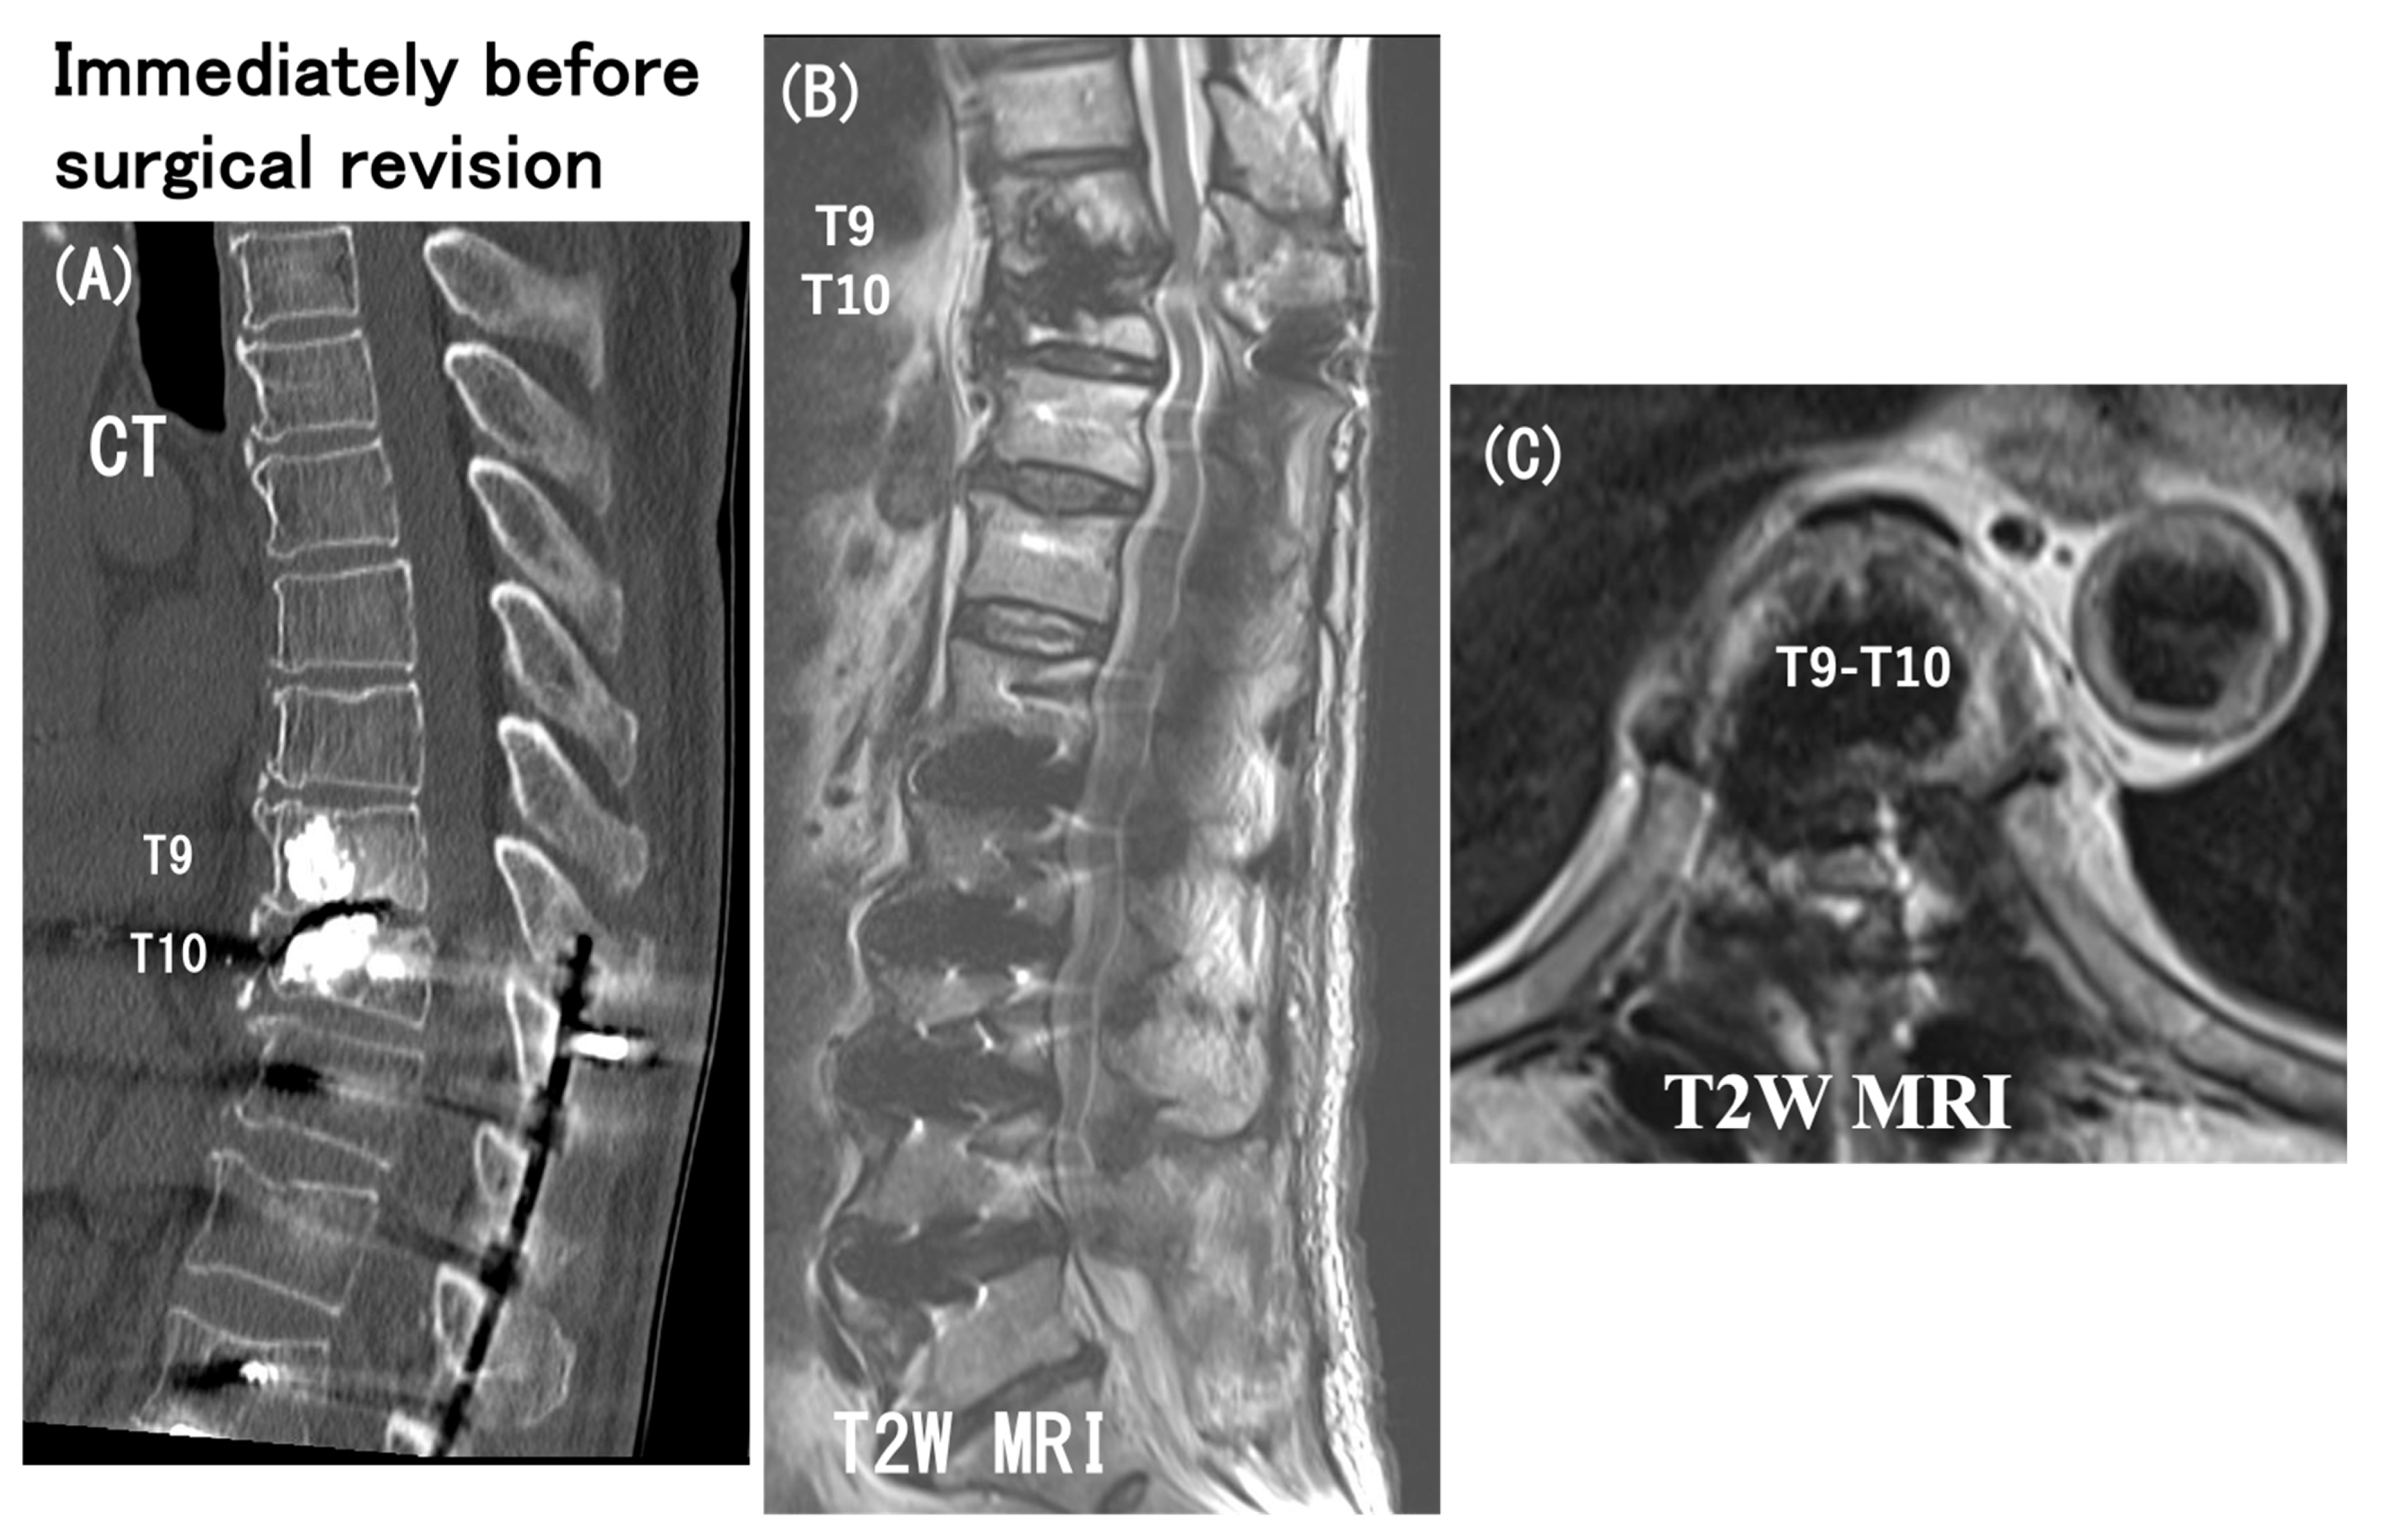

3.6. Case Presentation

- Case no. 6

- 2.

- Case no. 4